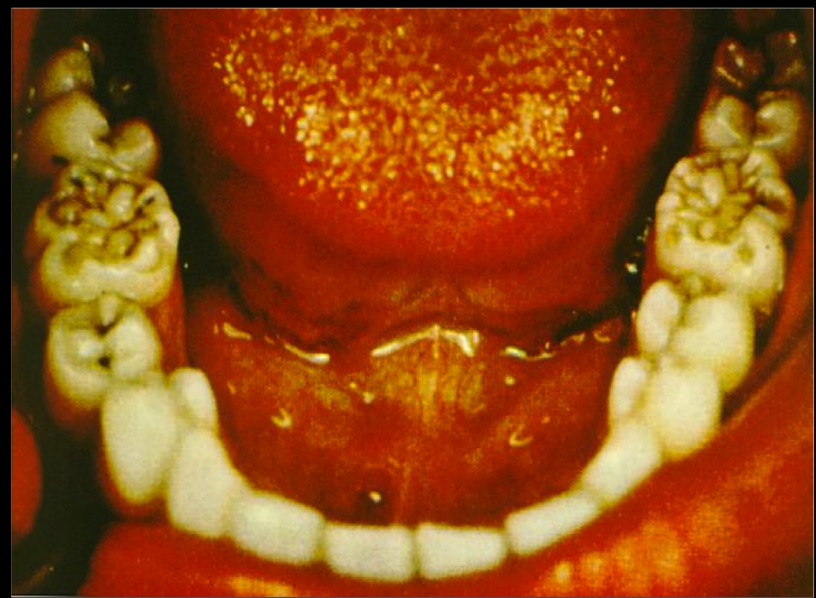

Oropharynx abnormalities such as hutchinson teeth and mulberry molars.

Mulberry molars:

Hutchinson teeth: